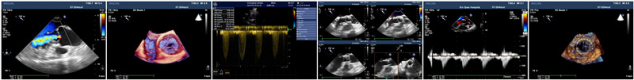

经导管主动脉瓣置换术(TAVR),是指将组装完备的人工主动脉瓣经导管置入到病变的主动脉瓣处,在功能上完成主动脉瓣的置换。自2002年首例成功以来,TAVR已成为老年主动脉瓣狭窄及反流患者的一线治疗手段。围手术期超心动图对TAVR手术起着至关重要的作用,能在术前对主动脉瓣结构和功能进行详细评估以及在术中、术后即刻监测和评估TAVR相关并发症,为手术保驾护航,不可替代。

自2017以来,我科在西南地区率先开展超声心动图在TAVR围手术期的应用,迄今已经完成检诊数量超过数千例,积累了丰富的临床经验。